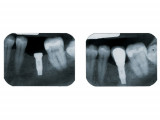

Implants

- Un implant dentaire est une racine artificielle placée par le chirurgien-dentiste dans l'os alvéolaire de l'un des maxillaires en remplacement de la racine d'une dent extraite et servant de support à une prothèse.

Sa forme est généralement cylindrique ou légèrement conique, ressemblant à une vis, en titane ou en zircone, avec une connexion au niveau supérieur, à l'emplacement de la gencive, pour permettre la pose d'un élément prothétique par vissage ou scellement.

Son diamètre varie entre 3 et 5mm et sa longueur entre 8 et 15mm.

Le choix se fait en fonction de l'emplacement, de la quantité d'os disponible, et des éléments anatomiques environnants à partir d'un examen radiologique et scanner de la zone à implanter.